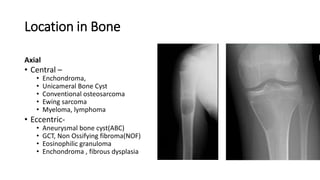

Location in Bone

Axial

• Central –

• Enchondroma,

• Unicameral Bone Cyst

• Conventional osteosarcoma

• Ewing sarcoma

• Myeloma, lymphoma

• Eccentric-

• Aneurysmal bone cyst(ABC)

• GCT, Non Ossifying fibroma(NOF)

• Eosinophilic granuloma

• Enchondroma , fibrous dysplasia